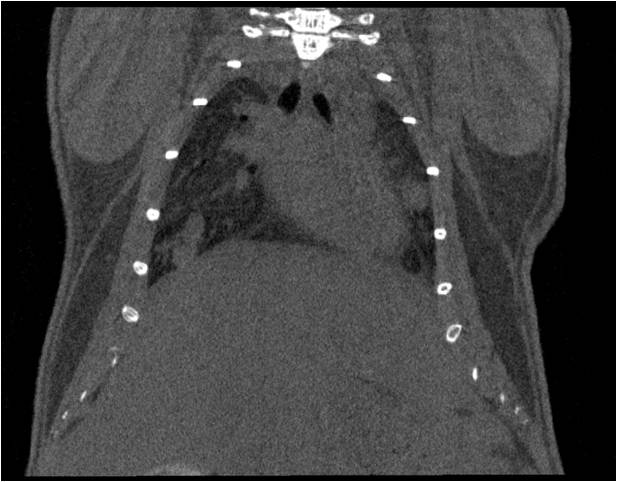

胸部和心血管的層析成像                                       胸部和心血管的3D圖像

心血管.jpg     心血管1.jpg